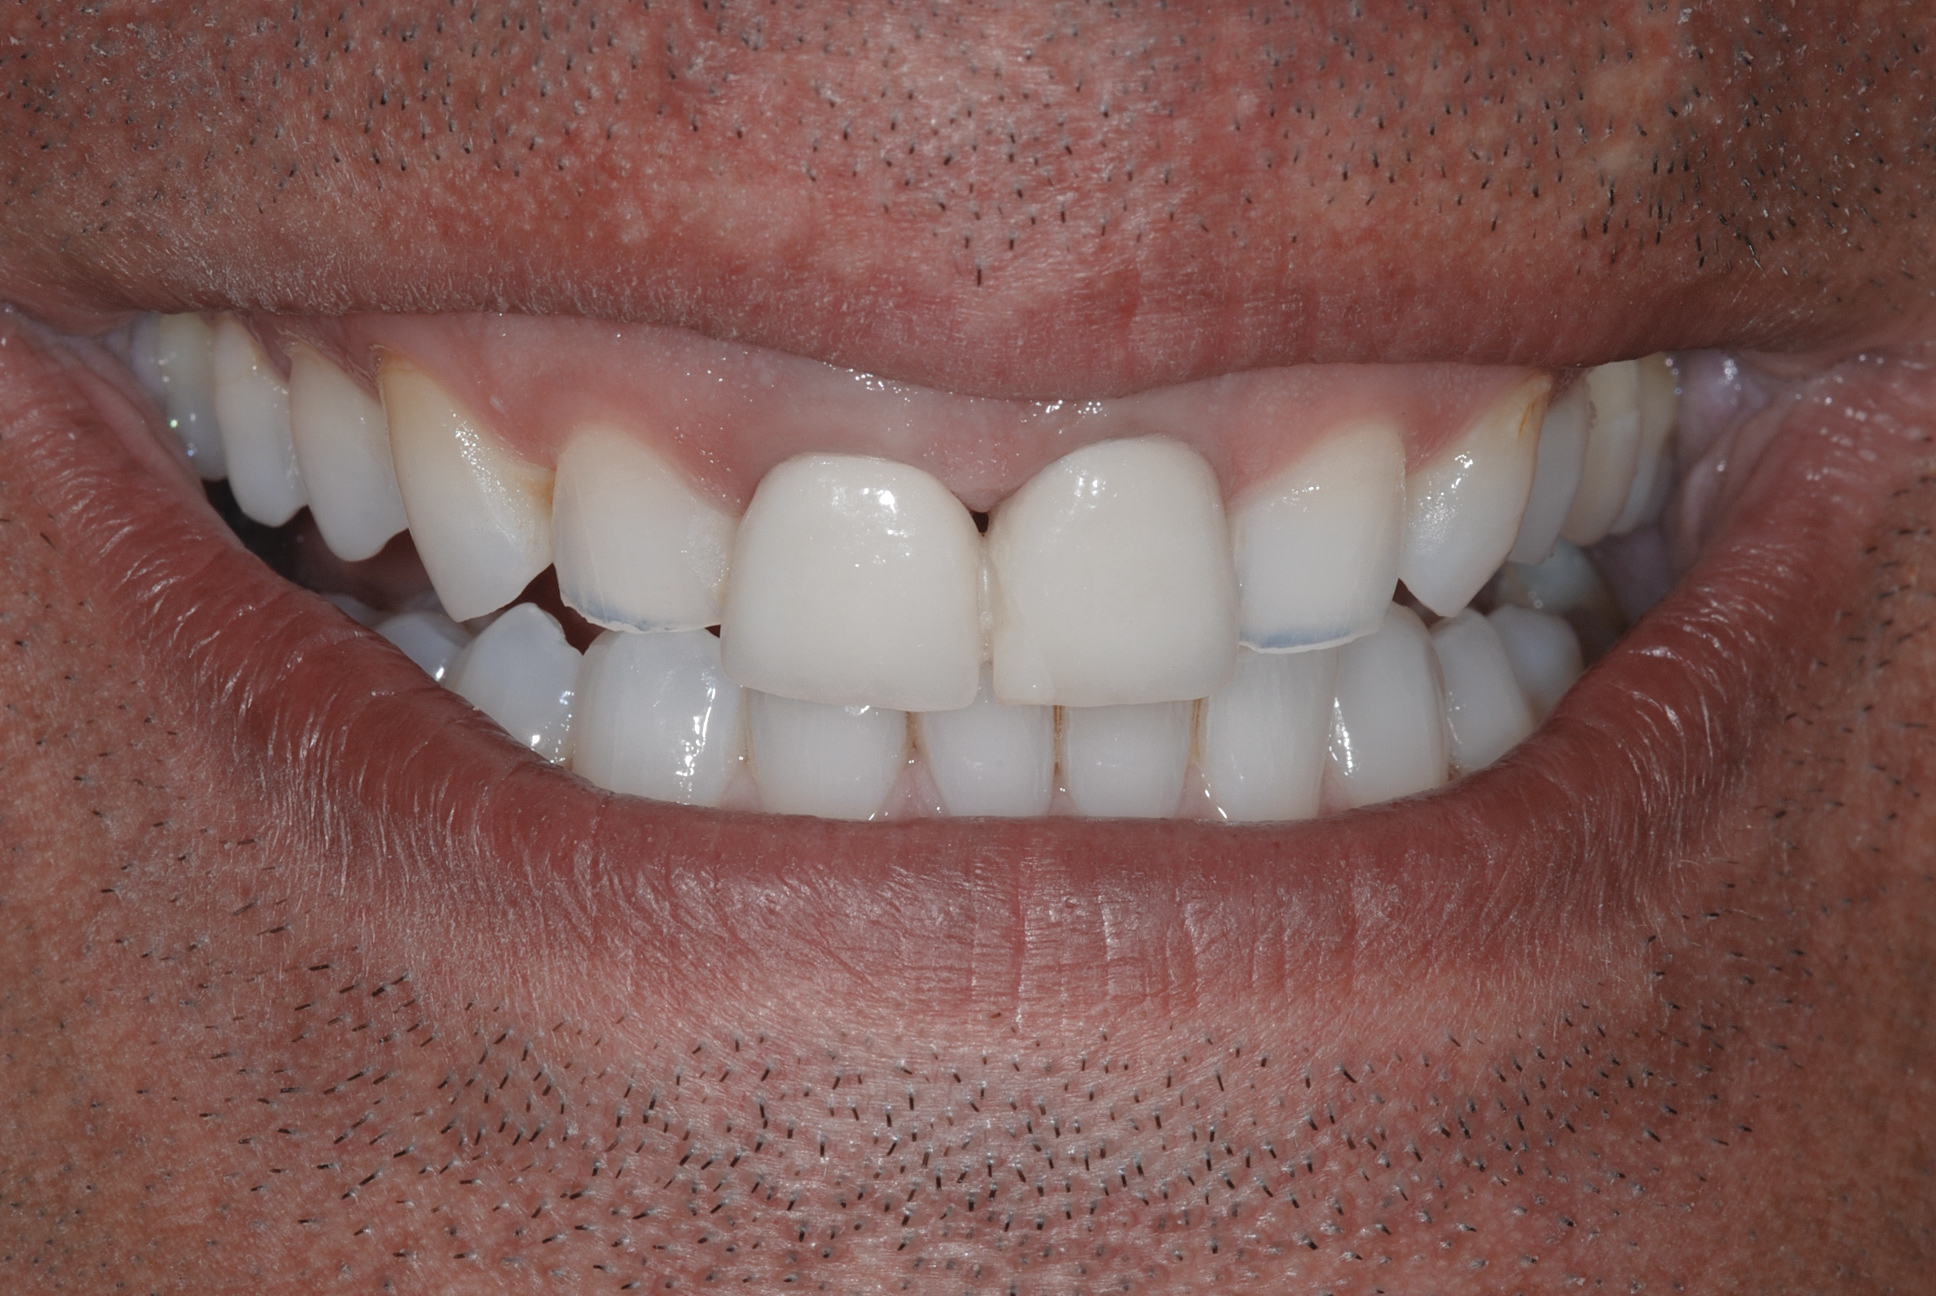

The authors consider GS and STS as two esthetic smile alterations that often coexist and have similar or coincident etio-anatomo–pathological origin and need to be diagnosed simultaneously with identical guidelines. Some of the causes of GS—including deep bite and overeruption and compensatory eruption (wear/erosion) in teeth, as well as gingival hyperplasia and altered active/passive eruption in gingiva—can also be identified in STS; however, vice versa is not the case. The aim of this article is to propose a classification of such adult patients and briefly describe a diagnostic process to use with this classification, and to identify a correct treatment plan that can lead to a successful treatment outcome (Figure 2).

Fig 2. Resolution of gummy smile after treatment in patient shown in Fig 1.

Figure 2